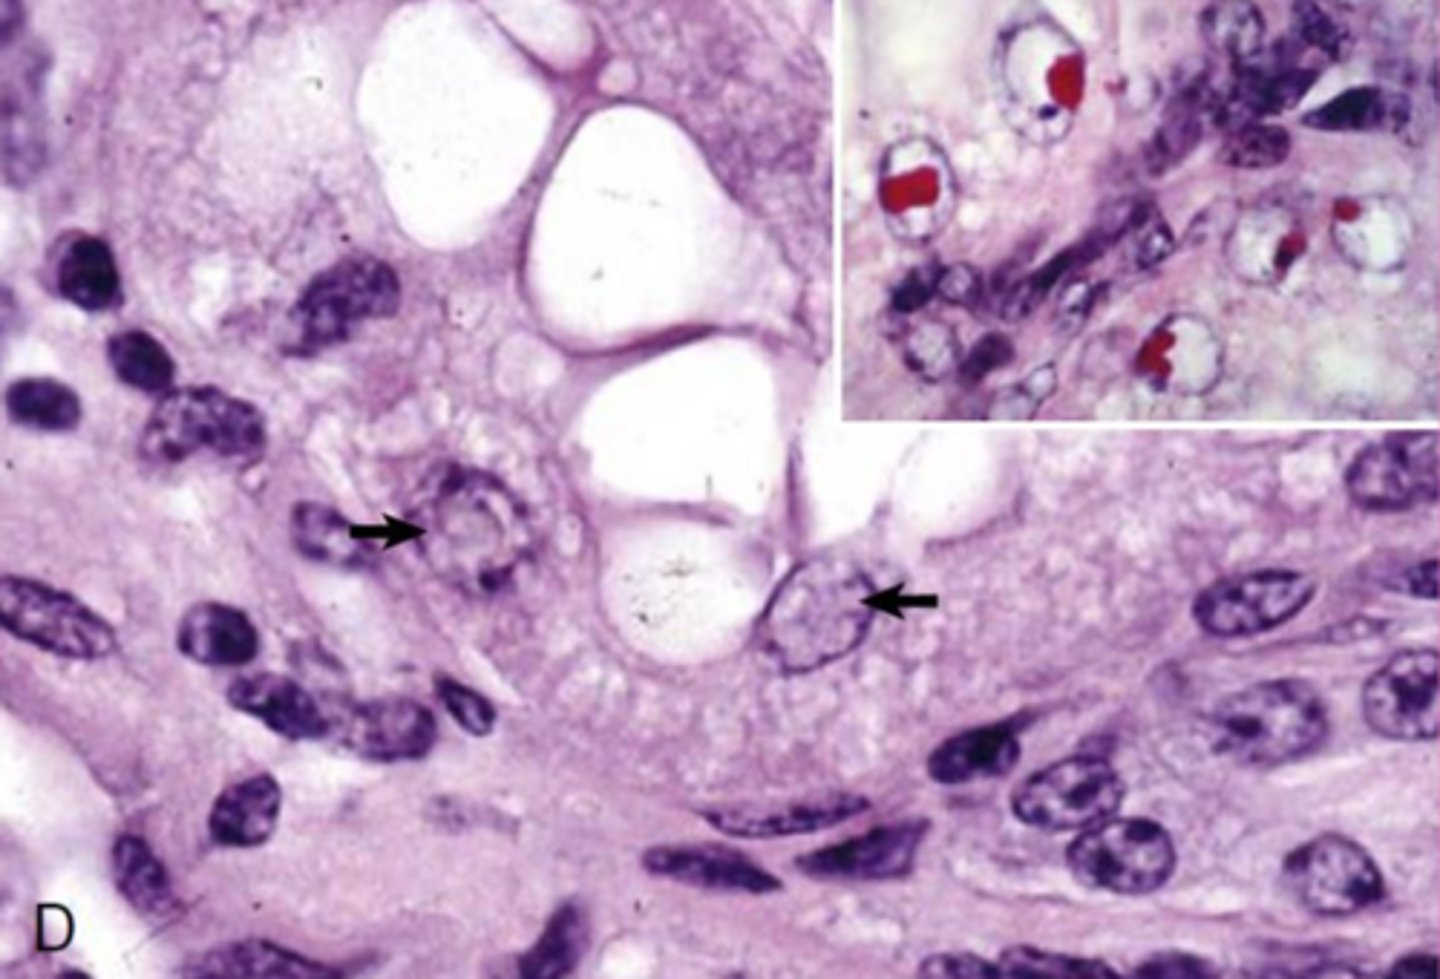

oil red O stain, staining lipid inclusions

What the hell is happening to these cells???

<p>What the hell is happening to these cells???</p>